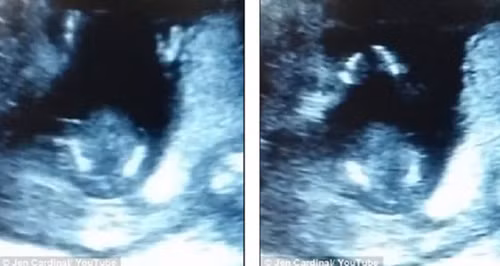

Jen Cardinal, bà mẹ sinh sống tại Olympia, Washington, Mỹ gần đây đã đăng tải một video siêu âm thai khiến người xem ngạc nhiên. Theo đó, trong video có thể thấy em bé 14 tuần tuổi đang vỗ tay như theo điệu nhạc.

Một thành viên trang Reddit đã chia sẻ hình ảnh siêu âm em bé giơ ngón tay cái như ra hiệu ăn mừng trong bụng mẹ. Hình ảnh này ngay lập tức thu hút 2 triệu lượt người xem trong vòng 24h đồng hồ.